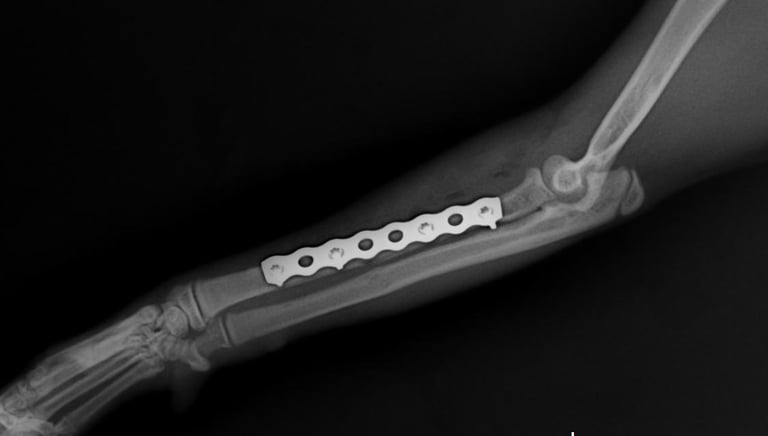

Un sistema de placa bloqueada es una técnica avanzada de fijación interna en la que los tornillos se bloquean directamente a la placa, formando una estructura rígida y estable.

A diferencia de las placas convencionales, este sistema no depende de la compresión contra el hueso, lo que permite:

Fijación de la placa al hueso

La placa se posiciona sobre el hueso afectado, adaptándose a su anatomía sin necesidad de comprimirlo directamente.

Inserción de tornillos bloqueados

Los tornillos se introducen atravesando la placa y se enroscan en ella, quedando firmemente anclados tanto al hueso como a la placa.

Formación de un sistema rígido

Al bloquearse los tornillos con la placa, se crea una estructura estable tipo “armazón” que no depende de la presión sobre el hueso.

Estabilización y cicatrización ósea

El sistema mantiene los fragmentos óseos alineados, permitiendo una adecuada recuperación y favoreciendo la cicatrización.

Los sistemas de placa bloqueada ofrecen ventajas significativas frente a métodos tradicionales, ya que combinan estabilidad mecánica con un enfoque más biológico de la reparación ósea.

Mayor estabilidad

La fijación entre tornillo y placa crea una estructura rígida que mantiene los fragmentos óseos alineados incluso en fracturas complejas.